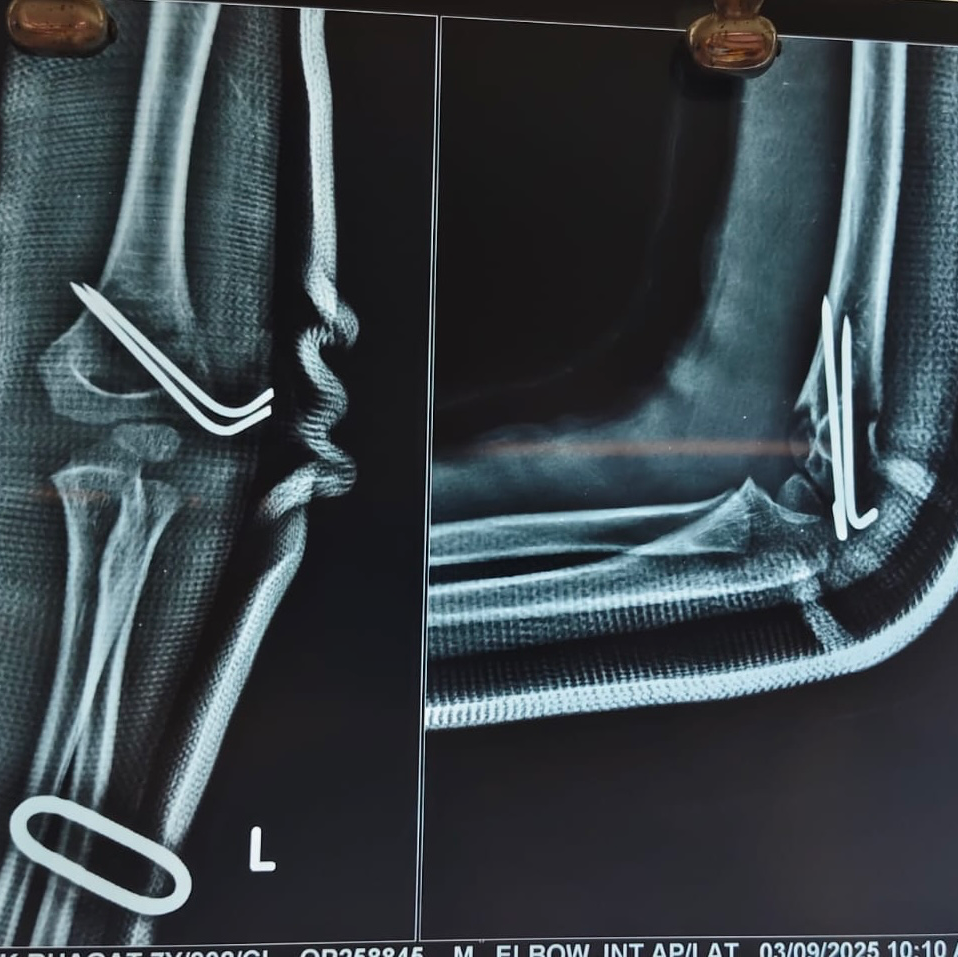

7 YEAR OLD BOY WITH SUPRACONDYLAR HUMERUS FRACTURE TREATED WITH K WIRE FIXATION